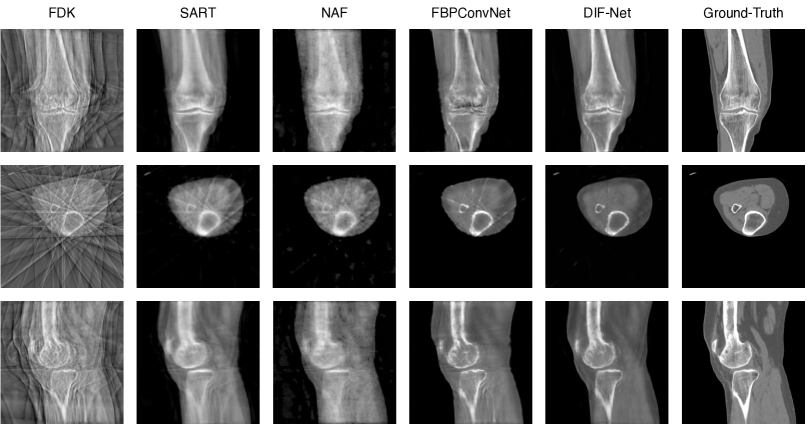

Visual comparison. The following Figure 5 shows visual comparison with different numbers of input views.

Refer to caption

Figure 5: Qualitative comparison of baseline models and our DIF-Net with different numbers of input views.

Performance. As shown in Table 1, we compare DIF-Net with four previous methods [1, 6, 22, 29] under the setting of reconstruction with different output resolutions (i.e., 1283,2563superscript1283superscript2563128^{3},256^{3}) and from different numbers of projection views (i.e., 6, 8, and 10). Experiments show that our proposed DIF-Net can reconstruct CBCT with high image quality even using only 6 projection views, which significantly outperforms previous works in terms of PSNR and SSIM values. More importantly, DIF-Net can be directly applied to reconstruct CT images with different output resolutions without the need for model retraining or modification. As visual results are shown in Figure 3, FDK [6] produces results with many streaking artifacts due to lack of sufficient projection views; SART [1] and NAF [29] produce results with good shape contours but lack detailed internal information; FBPConvNet [11] reconstructs good shapes and moderate details, but there are still some streaking artifacts remaining; our proposed DIF-Net can reconstruct high-quality CT with better shape contour, clearer internal information, and fewer artifacts. More visual comparisons of the number of input views are given in the supplementary material.